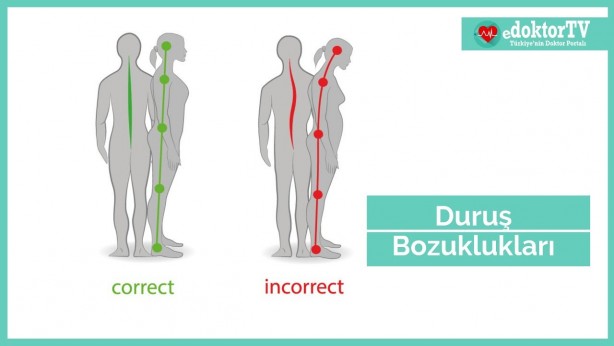

Pandemi dönemi için uzman isim uyardı: Buna dikkat etmezseniz boyunuz kısalabilir!

Duruş bozukluklarının fiziksel ve ruhsal olarak birçok soruna yol açabileceğini belirten Fiziksel Tıp ve Rehabilitasyon Uzmanı Dr. Esin Selimoğlu, yanlış duruş pozisyonlarının, boy kısalmasına dahi neden olabileceğini söyledi.